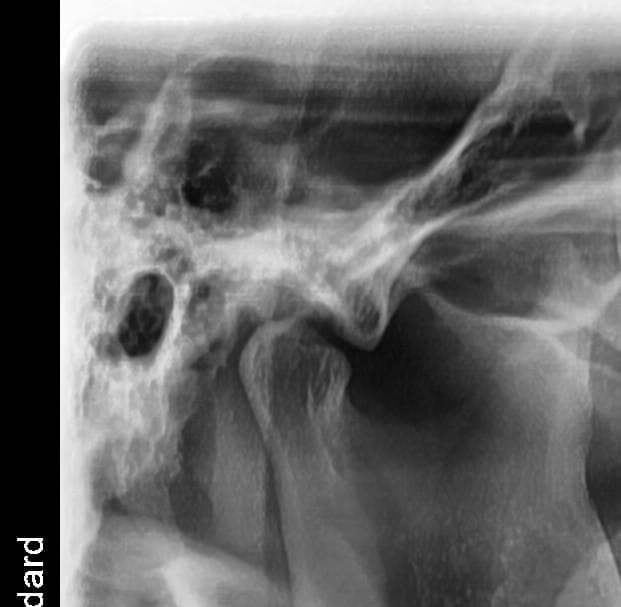

왼쪽 턱관절의 condyle 모양이 다소 각이져 있긴 한데 심한 턱관절염으로 보이진 않습니다. 딱딱한 음식 피하시고, 턱 마사지 해주세요 증상이 그래도 지속되면 구강내과 가보세요